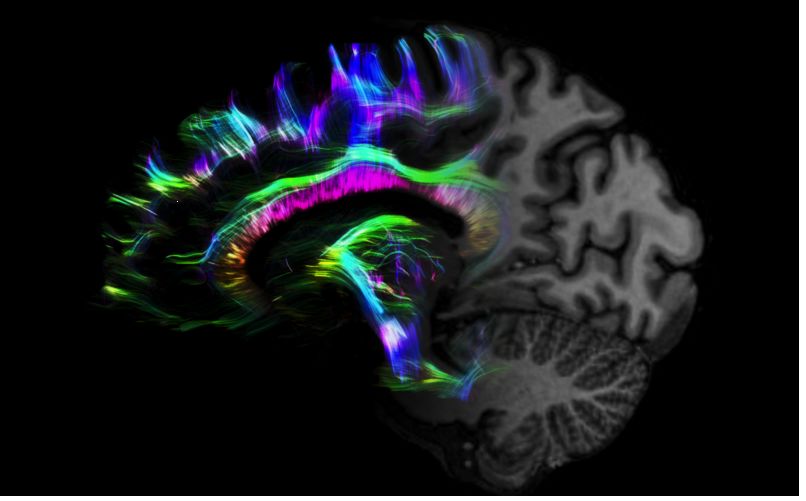

1毫米的各向同性分辨率DTI:神經(jīng)纖維束的交叉細(xì)節(jié)顯示